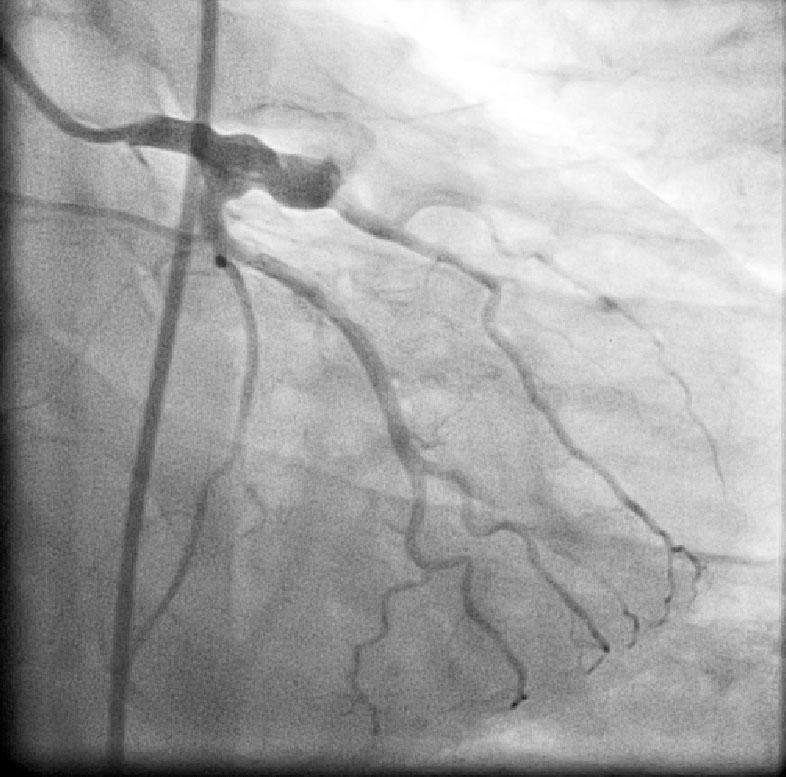

CABG in Kawasakis with Coronary Aneurysms

Angiogram prior to Primary PTCA